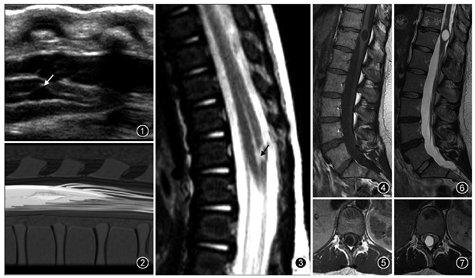

超声是诊断胎儿或新生儿第五脑室的一种常用检查方法[12](图1,图2,图3)。第五脑室在超声矢状切面图上显示为脊髓圆锥区域囊状扩张的低回声区并可与中央管相通,在超声横断切面图上表现为扩张的低回声囊腔且与周围脊髓组织有着较为清楚的分界。MR检查为诊断第五脑室的主要手段。第五脑室在MRI上通常表现为脊髓圆锥内边缘清楚的卵圆形囊腔,形态规则,囊壁光整,且与周围正常的脊髓组织分界清楚,囊内为T1WI低(图4,图5)、T2WI(图6,图7)高的脑脊液信号,囊内分隔及囊周水肿性改变比较少见,增强扫描后囊壁不强化。第五脑室需要与位于脊髓圆锥的囊性肿瘤如室管膜瘤、星形细胞瘤以及脓肿相鉴别,囊性肿瘤和脓肿的囊壁通常有不同程度的强化。脊髓圆锥的转移瘤很少见,MRI表现通常为肿瘤强化且周围伴有明显水肿[13]。脊髓背侧的严重损伤也可发展为囊性病灶,但目前报道的大多数第五脑室病例并无外伤病史[6]。脊髓内的表皮样囊肿和皮样囊肿由于成分复杂导致MRI表现多变[14],而第五脑室的MRI表现单一。